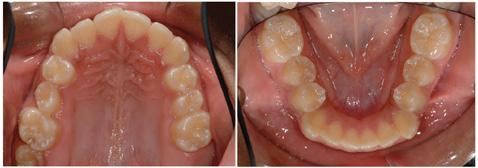

Maximum intercuspation occurred following an anterior functional shift of the mandible and then vertical bite closure. The molar and canine relationship is Class III bilaterally, obviously worse in centric occlusion compared to centric relation. The INITIAL occlusal photographs (Figure 2) show mild maxillary anterior crowding, undersized and unusual shaped second premolars, and no apparent Class III compensation. A similar amount of crowding is seen in the mandibular arch, however, the incisors exhibit some visual Class III compensation.

The FINAL intraoral photographs (Figure 6) highlight well aligned teeth, Class I canine occlusion bilaterally, and ideal overjet and overbite. Gingival revision of tooth #4 may be beneficial in the future if there is a delay in passive eruption following rotational correction of this maxillary right second premolar. Tooth #13 is more attractive.